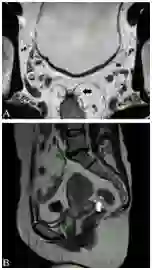

肿瘤复发通常在术后2年,MRI是显示复发、盆腔播散和淋巴结转移的金标准(图16、17),圆形或突出的损害边缘提示肿瘤复发,直角边缘提示纤维化。术后并发症,如吻合口漏、出血、瘘和盆腔脓肿与积液(图18),钆增强图像具有诊断作用,不过检测上述并发症时CT优于MRI。

图16  75岁男性直肠癌复发,放化疗后8个月轴位T2加权像显示直肠腔内真菌样肿物(长箭头),伴骶骨前软组织复发且累及骶骨(箭头)。

图17  41岁男性直肠癌腹会阴(AP)切除术后1年复发。A.轴位T2加权像显示右侧盆壁复发肿瘤为锯齿状软组织影(长箭头),可见骶前疤痕(箭头)。B.冠状T1加权钆增强像显示复发肿瘤增强(长箭头),右侧阴部神经周围侵犯(箭头);C.轴位T1加权钆增强像显示右侧阴部管的阴部神经周围侵犯(长箭头)。

图18  35岁女性直肠癌放疗后。A.轴位T2加权像直肠右侧肿物(箭头),右侧直肠系膜内脓肿(长箭头),脓腔内见碎片和低密度信号气泡;B.轴位T1加权钆增强像显示直肠肿瘤增强(箭头),直肠系膜右侧脓肿边缘增强(长箭头)。